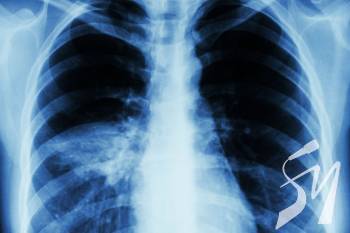

Діагностувати пневмонію допомагають рентгенографія грудної клітки, комп’ютерна томографія, пульсоксиметрія, аналіз крові та мокротиння у сукупності з клінічними ознаками.